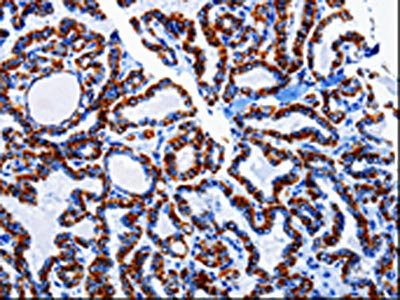

• The image on the left is immunohistochemistry of paraffin-embedded Human thyroid cancer tissue using CSB-PA797497(ARL6 Antibody) at dilution 1/10, on the right is treated with fusion protein. (Original magnification: ×200)